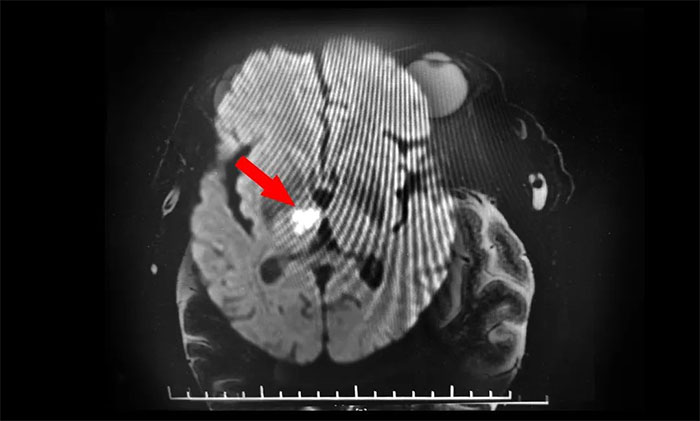

再次行MR头颅MRI平扫+增强+DWI+MRA,提示脑干、右侧丘脑及双侧大脑半球白质多发梗塞灶及缺血灶(中脑及右侧丘脑梗塞急性期),右侧大脑后动脉狭窄,右MCA-M1段狭窄。至此,该患者双侧动眼神经损伤原因诊断明确,病因为右侧中脑梗死所致,责任血管为右PCA-P1的狭窄致中脑旁正中动脉闭塞,为动眼红核综合征,导致同侧动眼神经麻痹伴对侧肢体共济失调,同时累及右丘脑旁正中动脉。

▲ DWI确诊脑干梗死

张静波主任指出,DWI是诊断急性脑梗死的有力武器,但是每个人的脑血管侧支循环不同,DWI没有固定的显影时间,特别是对于后循环的脑梗死,DWI更容易出现阴性,这些都给诊断增加了难度。